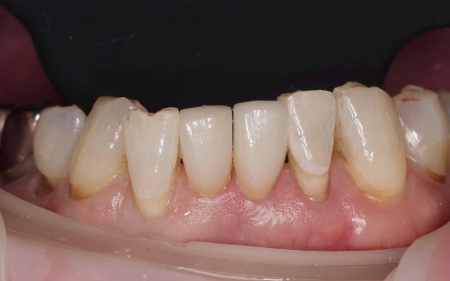

60代女性 すり減った前歯をセラミックのラミネートベニアで修復した症例

それぞれのメリット・デメリットを丁寧に説明したうえで、今回は歯を削る量をできるだけ抑えられる②のラミネートベニアを提案し、同意いただきました。

まずセラミックの薄い板を貼り付けるためのスペースを確保するため、前歯の表面をわずかに削る処置を行いました。

その後、歯の形を正確に再現するための型取りを行い、完成までの間は歯を保護する目的で仮歯を装着しています。

後日、完成したセラミックの薄い板を実際に歯に合わせ、色味や形、噛み合わせに問題がないかを確認したうえで歯科用の接着セメントを用いて歯の表面に貼り付け、治療を終了しました。